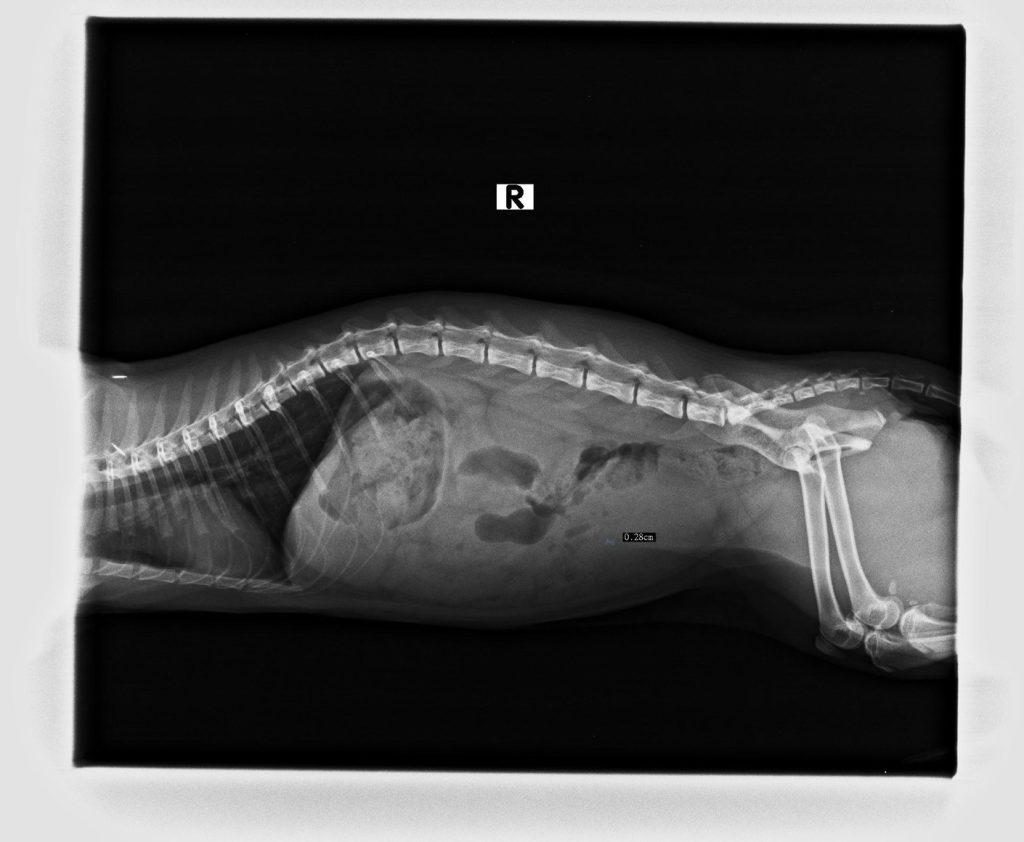

內視鏡急診案例(二)

就診對象:博美犬

就診原因:

拍攝X光發現食道異物博美吃完零食後一直咳嗽停不下來,飼主發現後緊急送至順心動物醫院急診。

臨床檢查:

拍攝X光發現食道異物。

治療方式:

緊急內視鏡手術夾出。

手術結果:

術後恢復良好。

注意:不要給予小型犬吃太硬或太大的東西。